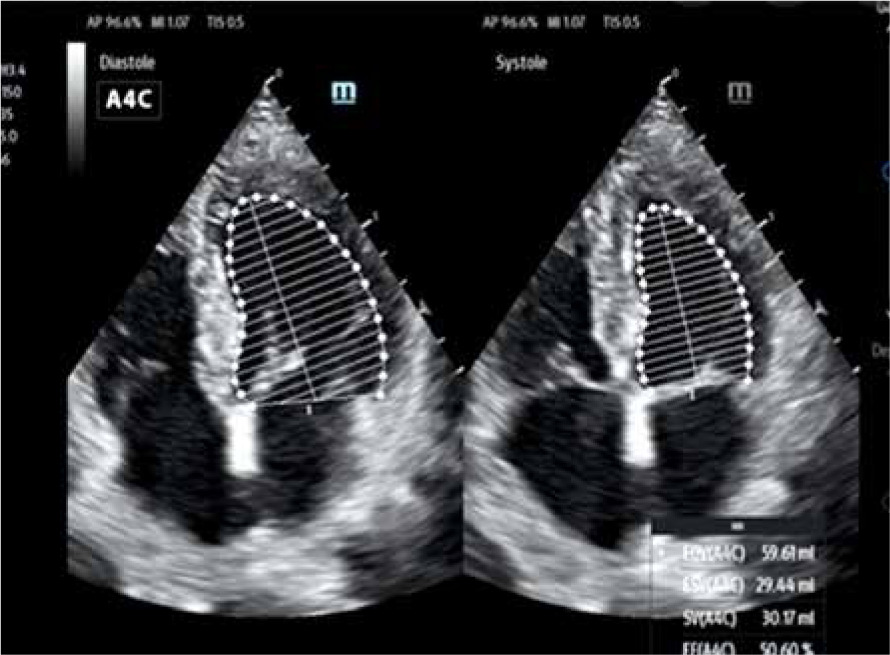

– AutoEF (Mindray/GE) is the system for automatic measurement of the left ventricular ejection fraction (LVEF), one of the most important parameters for the evaluation of cardiac efficiency. Similarly to SmartVTI, the measurement is fully automatic. This time, however, the only task of the operator is to obtain proper apical, 4-chamber or 2-chamber projection and then to click on the AutoEF icon to launch automatic measurement of the ejection fraction (EF). Following this, the system automatically outlines the systolic and diastolic left ventricle in real time. Making use of Simpson’s method (biplane disk summation), the system presents measurement of the end-diastolic volume (EDV) and EF. This ensures the objective character of the EF evaluation made by the operator [8]. The usefulness of such methods depends on the sonoanatomic condition of the patient (Figure 4).

FIGURE 4

Graphic presentation of AutoEF software – automatic fraction measurement (author’s own source)